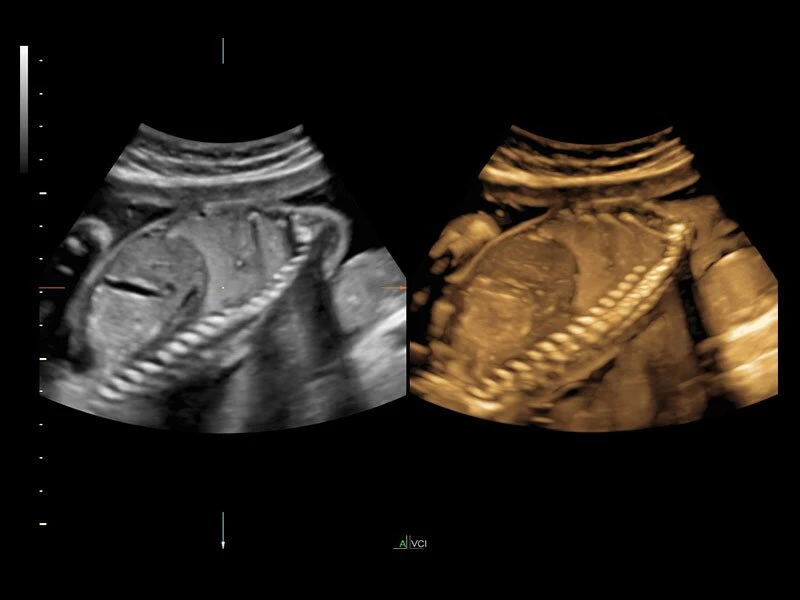

- Усовершенствованный режим объемной визуализации с контрастированием (Volume Contrast Imaging, VCI) и опция OmniView

- Повышает контрастное разрешение и улучшает визуализацию области интереса в любой плоскости сечения, даже при исследовании структур неправильной формы.

- SonoRenderlive

- Улучшает объемную визуализацию за счет автоматического определения линии начала реконструкции при изображении поверхностей. При исследовании в режиме 4D функция SonoRenderlive непрерывно обновляет положение исходной линии с учетом движений плода.

- Режим 3D SonoRenderLive – инновационная система, позволяющая определять четкие границы лица и конечностей плода в объеме, избавляясь при этом от лишних артефактов, шума и помех.